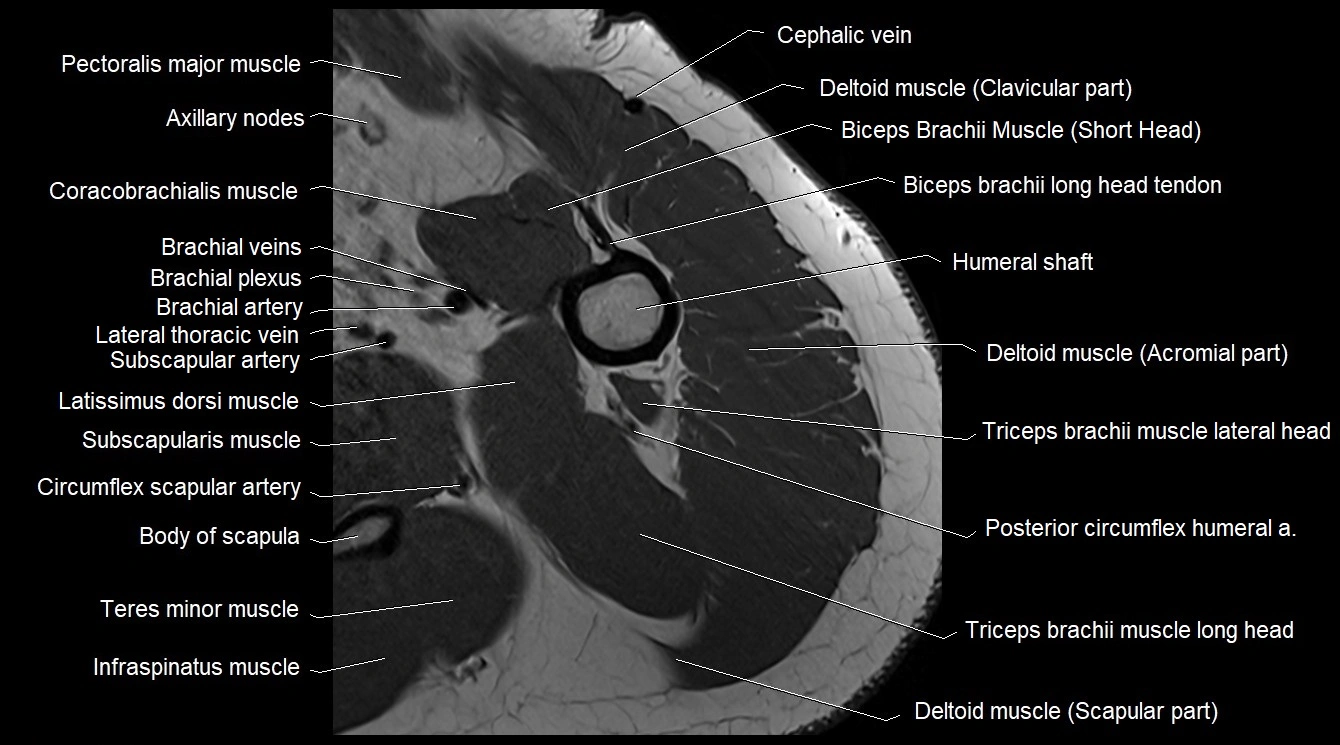

MRI image